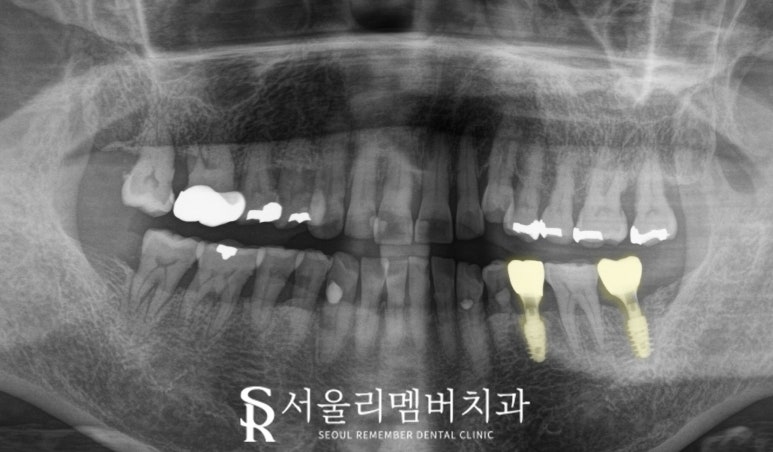

이 케이스는 크랙이 있는 37번을 발치하고

동시에 뼈이식과 픽스처 식립을 하였습니다.

발치 즉시 시행한다면

치료 기간을 단축할 수 있으며,

잇몸뼈의 흡수를 최소화할 수 있다는

장점이 있습니다.

그리고 발치와 부위에 인공뼈 이식재를 넣어주면

픽스처 주변의 뼈 재생을 촉진하고,

장기적인 안정성을 확보합니다.

골 유착 및 보철 수복

식립 후 2개월 이상 동안

골 유착이 될 수 있도록

기다려줍니다.

이것은 픽스처와 주변 뼈가

단단히 결합하는 데에

매우 중요한 시기로서

이 기간 동안 환자는 정기 검진을 통해

치유 상태를 확인하고,

과도한 자극이나 압력을 피하는 것이 중요합니다.

최종 보철이 장착된 모습을 보면

본래의 저작 기능을 모두 회복하였으며

임플란트의 장점인

독립적인 보철 제작이 가능하기에

사이에 치실 같은 구강위생용품 사용도 가능합니다.

올해부터 상부 보철이

PFM에서 지르코니아로 업그레이드되어

심미성과 강도를 모두 갖춘 재료로

만들 수도 있답니다.